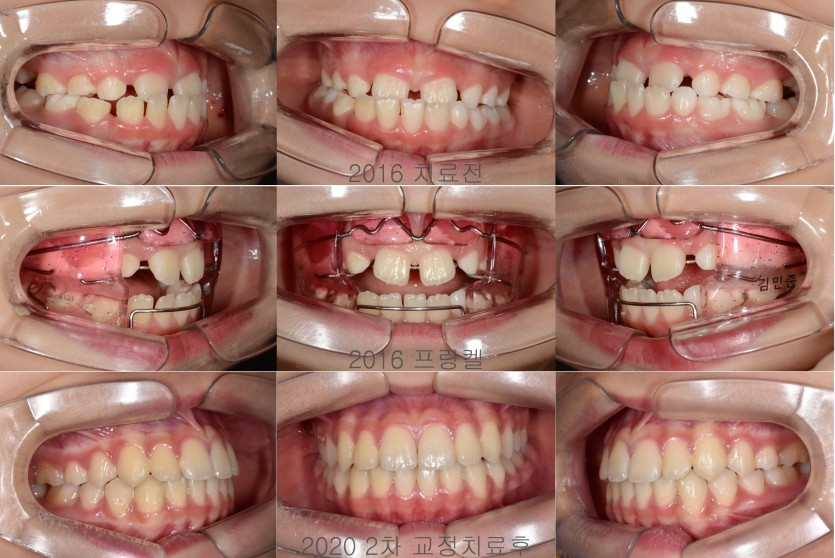

반대교합의 프랑켈 교정장치 치료 279회

초1때 전치가 맹출하고 앞니 반대교합이 관찰되는 경우에서

반대교합이 골격적 편차에 의한 것이 아니라

치아의 맹출방향 이상에 의한 것이라면

프랑켈 장치를 이용해 비교적 간단하게 해결할 수 있습니다.